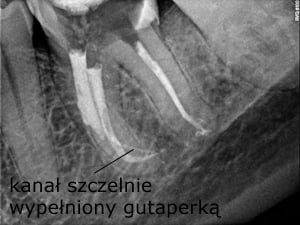

27-latni pacjent zgłosił się do naszej placówki z prośbą o pomoc polegającą na kontynuacji leczenia kanałowego, trwającego już wiele miesięcy. Leczenie przedłużało się z powodu powikłania w postaci złamanego narzędzia endodontycznego, które uniemożliwiało dezynfekcję systemu kanałowego na całej długości. Dodatkową trudnością była lokalizacja narzędzia w połowie długości korzenia za krzywizną kanału, co uniemożliwiało jego widoczność w mikroskopie. Podjęto próbę ominięcia („by passa”) narzędzia, co niestety nie powiodło się. Nieocenioną pomocą w tym precyzyjnym zabiegu okazała się tomografia wolumetryczna, która „sięgała, gdzie wzrok nie sięgał” i ułatwiła bezpieczne usunięcie narzędzia, a następnie pełną dezynfekcję i szczelne wypełnienie systemu korzeniowego. Zabieg trwał 4 godziny (2 wizyty po 2 godziny) i dzięki olbrzymiej cierpliwości pacjenta i precyzji operatora zakończył się sukcesem.